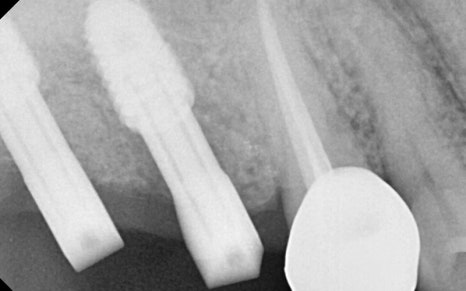

✅ Second surgery completed

After confirming that the implant had integrated well with the jawbone,

we proceeded with the second surgery,

and

After taking impressions, (left image)

we attached a custom abutment. (right image)